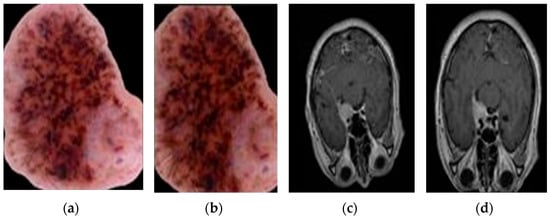

- Combined Dataset (described in Section 3.1): We leverage a rich dataset that combines skin lesion images from the publicly accessible Human Against Machine (HAM) archive, and brain MRI scans from the BraTS 2020 challenge [26,27]. All training and test images were uniformly formatted in RGB with a fixed size of 600 × 450 pixels. Figure 3a,b illustrate dermoscopic skin lesions from the HAM archive. Figure 3c depicts an MRI brain scan from the BraTS 2020 dataset.

- Data Augmentation: To address potential limitations in dataset size and variations in image quality (e.g., illumination errors, inconsistent staining, image noise), we employ data augmentation techniques described in Section 3.2. These techniques, such as rotation, flipping, and scaling, artificially expand the Dataset and help the model learn from a wider range of image presentations. The effectiveness of data augmentation is visually demonstrated in Figure 4 and Figure 5, which show the original images alongside their augmented counterparts.